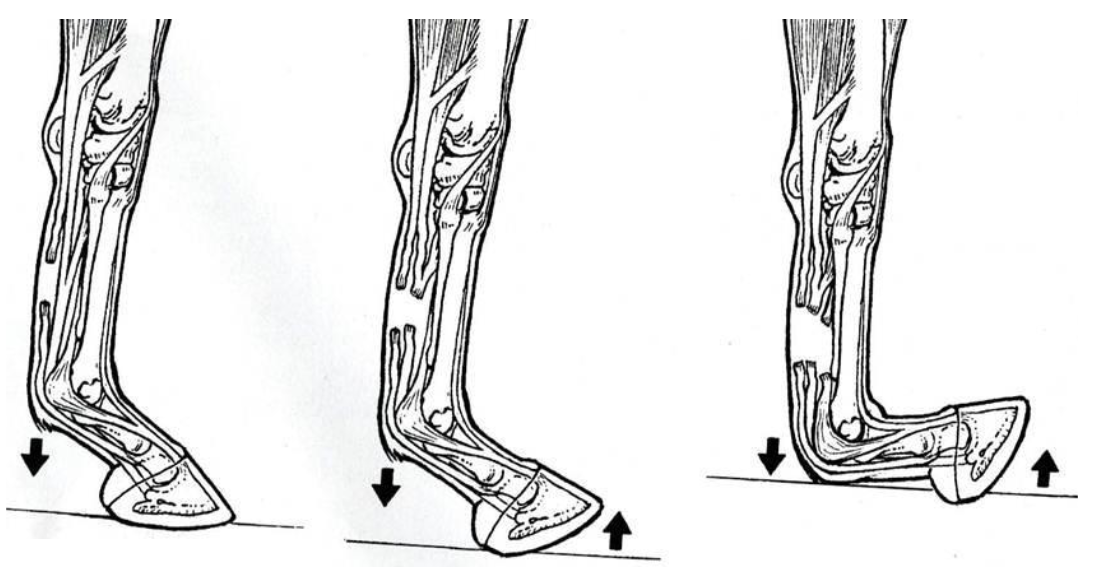

the equine foot

P3 is suspended within the hoof by laminae

-epidermal laminae attached to hoof wall

-dermal laminae attached to P3

laminitis (founder)

inflammation of the laminae

degeneration of the laminae

can lead to rotation of P3 (more common) or sinking of P3 within hoof capsule (worse, can feel a depression)w

what is this condition

laminitis, rotation of P3

what is this

a normal hoof, note parallel angle